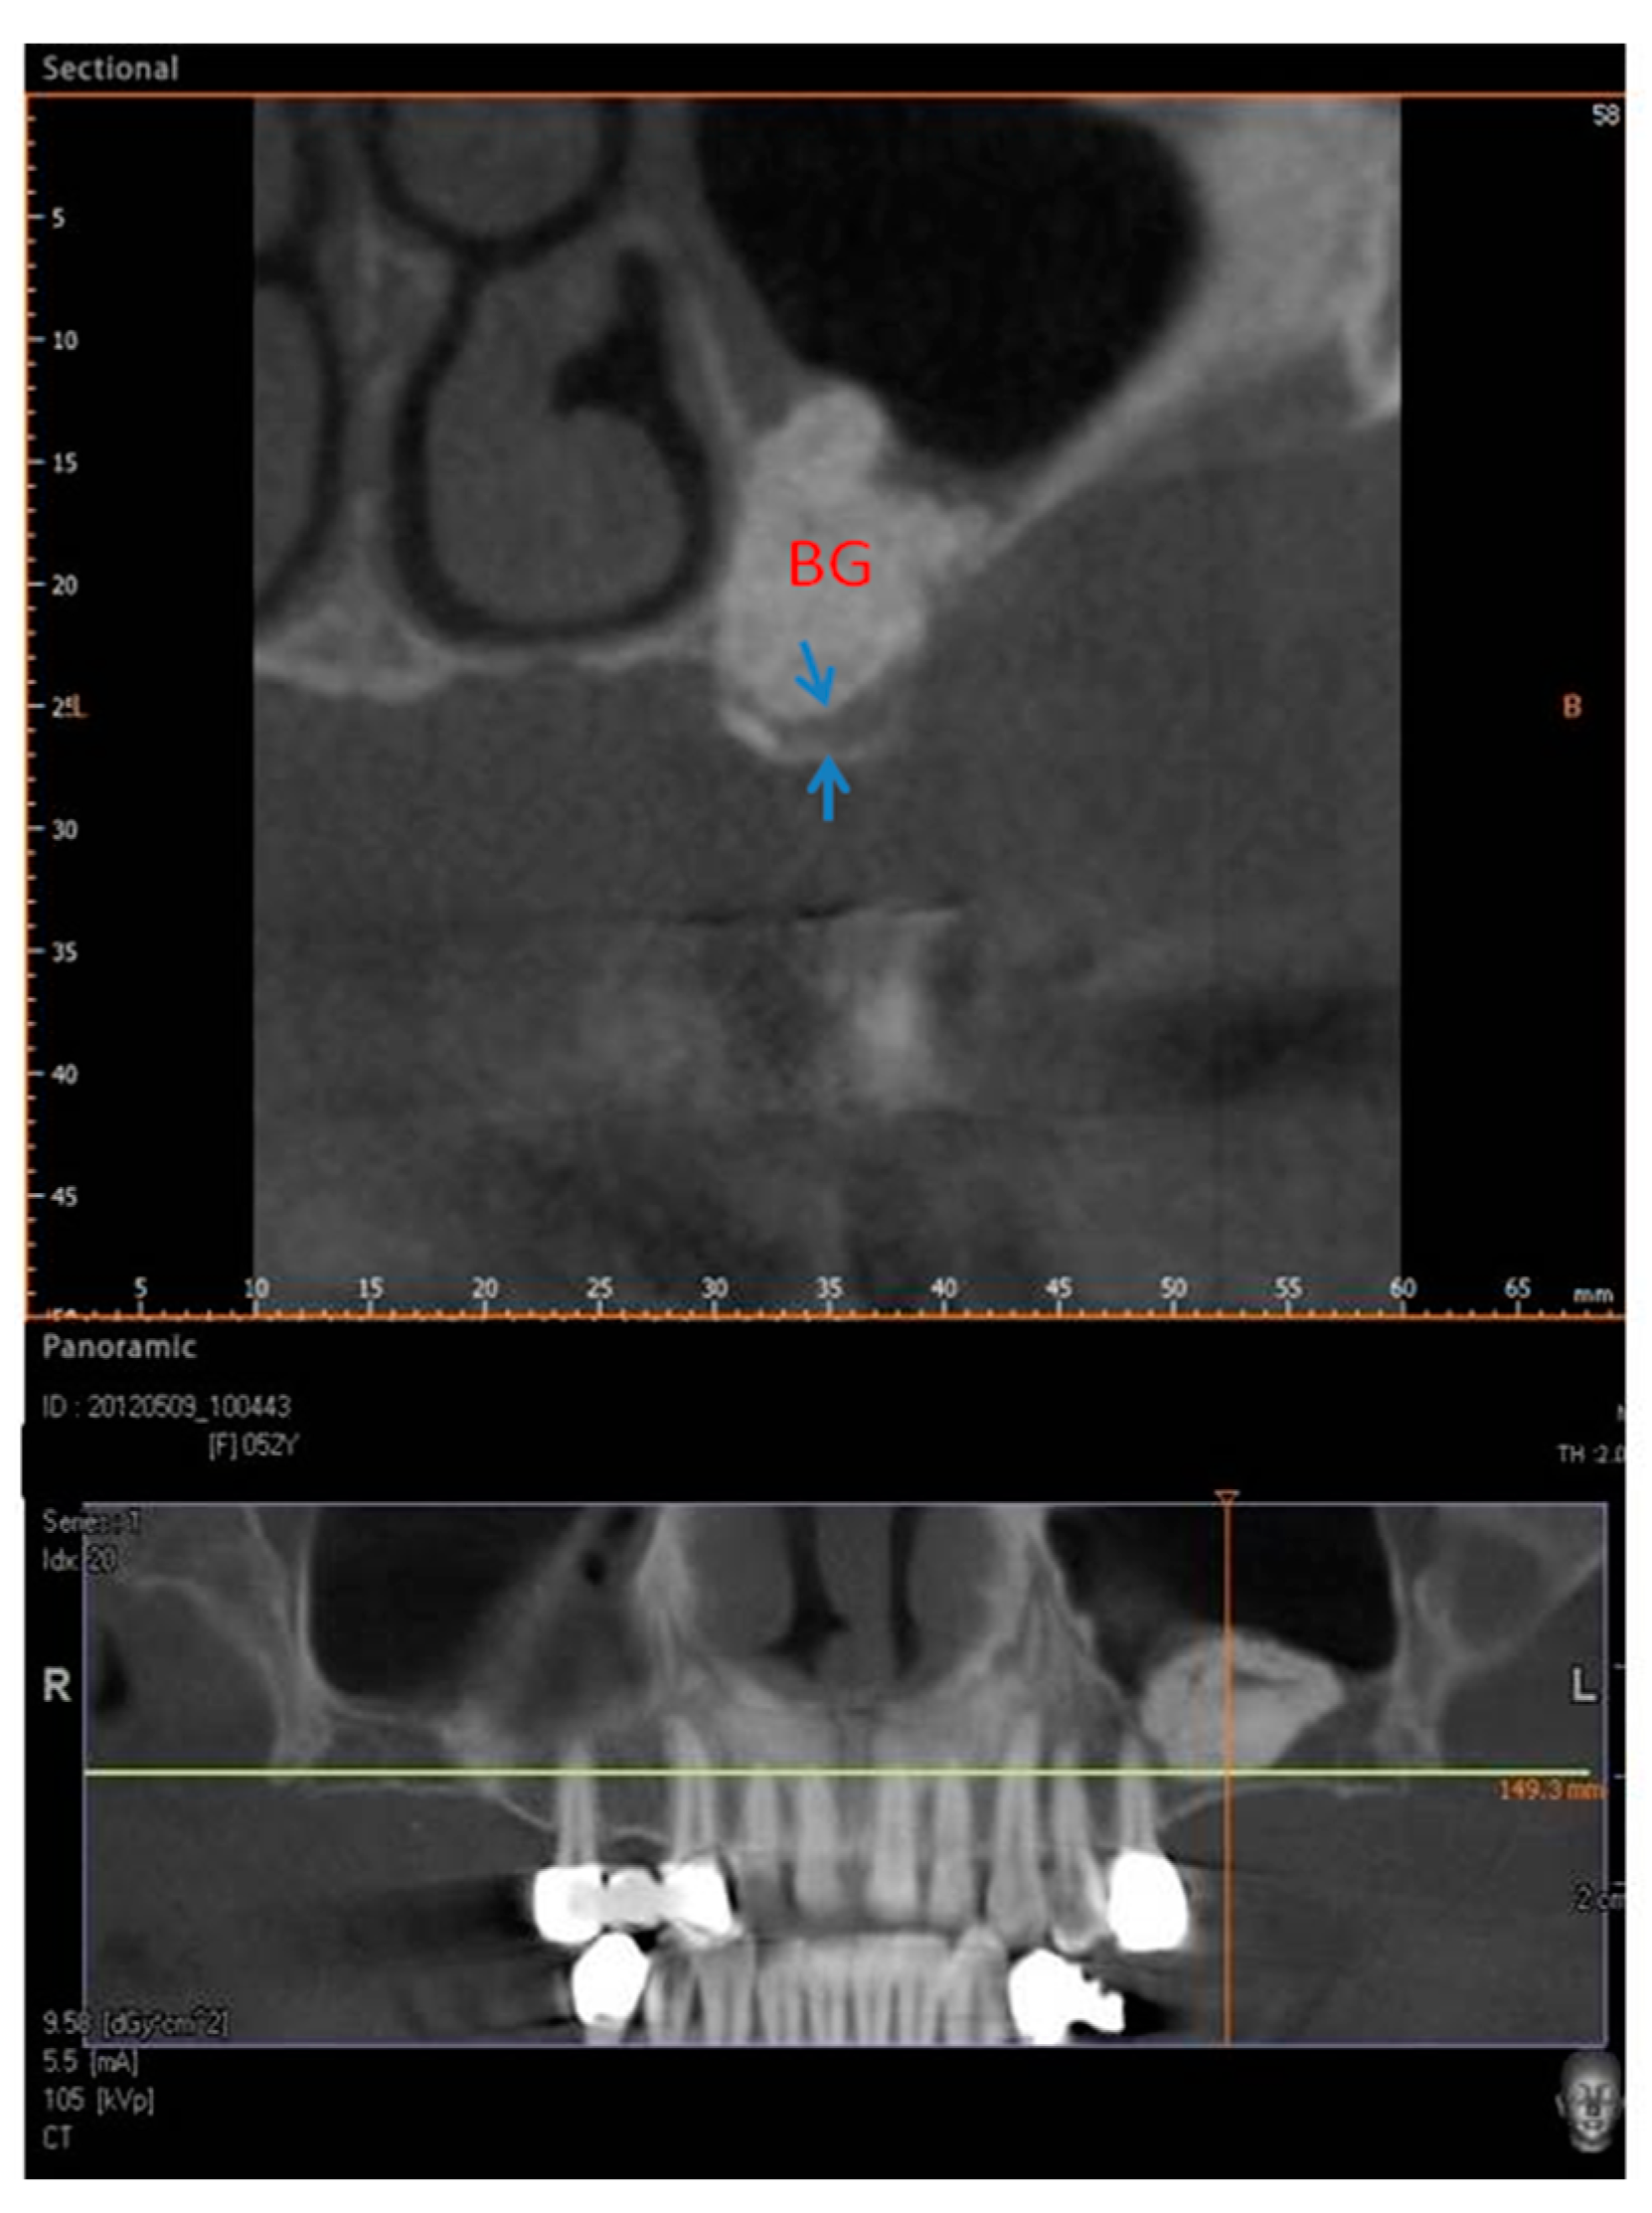

2.1. Group I

2.2. Group II

4. Materials and Methods